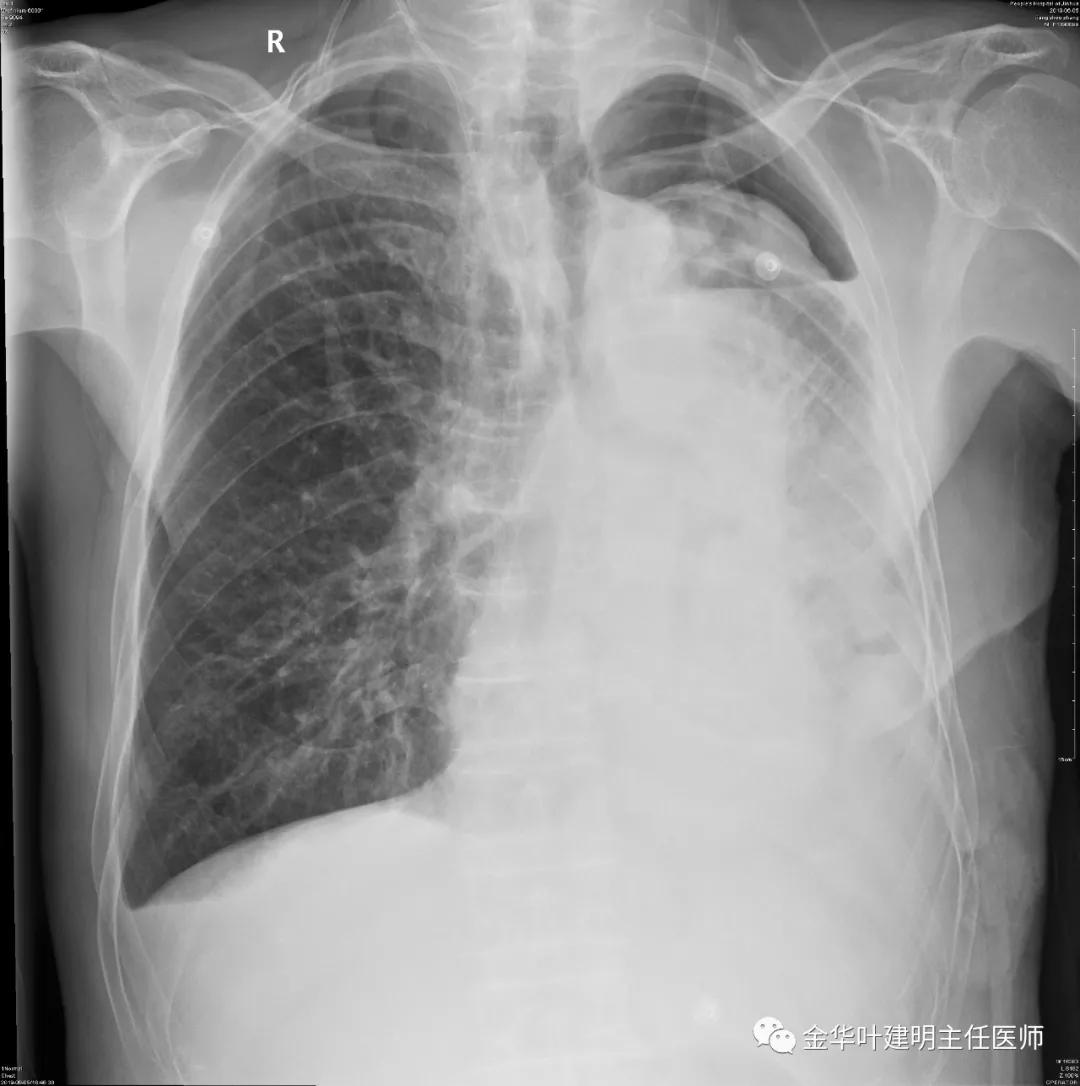

5.31下午7时,从早上开始算胸引700毫升,共900毫升;予以查床边,胸片,结果如下:

考虑左侧大量胸腔积液,遂进一步胸部CT检查: